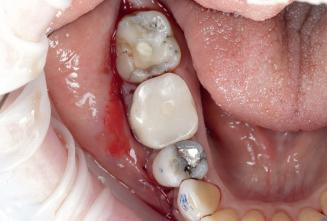

Case 2: Posterior tooth restoration with composite

Restorations with Beautifil II LS, Beautifil Flow Plus X and OneGloss by Erik-Jan Muts, M.Sc., Netherlands